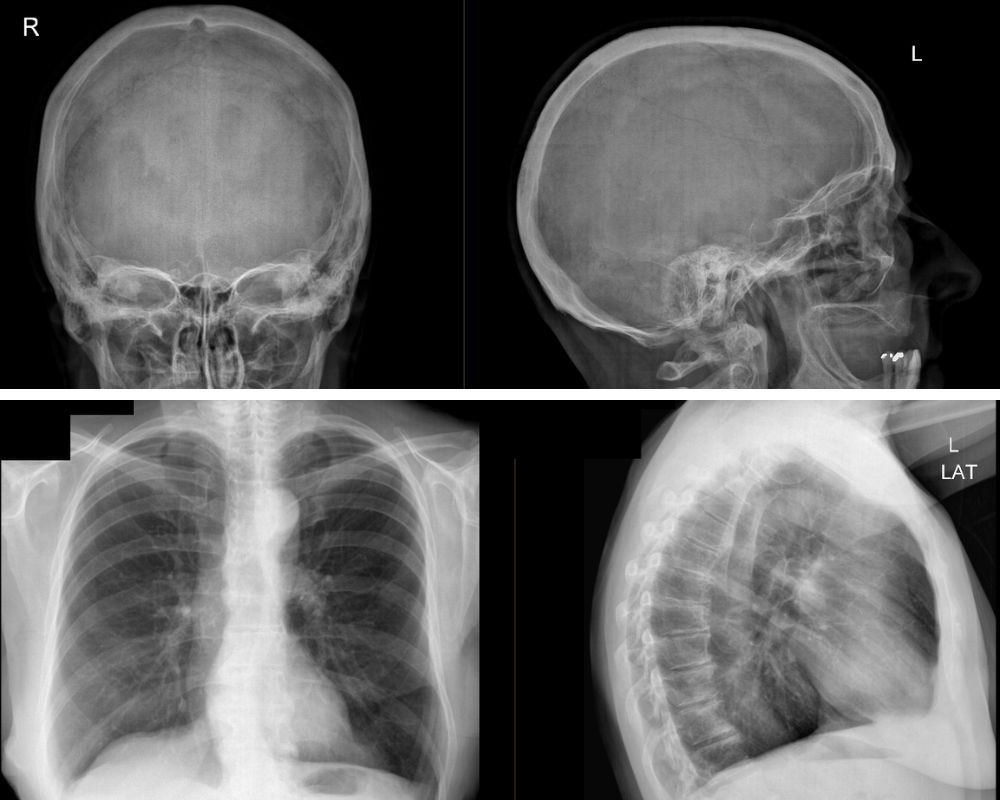

A Radiografia do Tórax é feita em inspiração.

Com frequência são solicitadas duas incidências: com o doente de frente (póstero-anterior) e de lado (o perfil esquerdo).

O doente deverá estar despido da cintura para cima para que não haja artefatos provocados pela roupa ou outros.